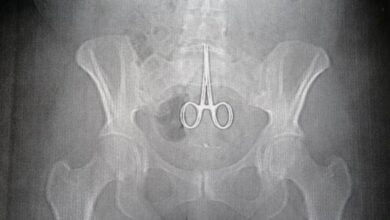

Divers, Elle se fait réopérer 7 ans après qu’on a oublié une paire de ciseaux dans son ventre

Cette dame sierra-léonaise a eu la vie sauve après qu’on lui a retiré une paire de ciseaux dans le ventre…